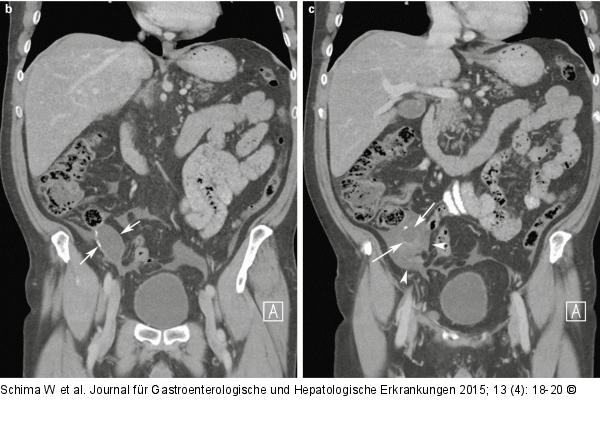

Abbildung 5b, c: MDCT Koronale Schichten der MDCT zeigen anschaulich die Mukozele der Appendix (Pfeile) und die abgekapselt imponierenden Flüssigkeitsansammlungen im Peritoneum (Pfeilspitzen). |

Koronale Schichten der MDCT zeigen anschaulich die Mukozele der Appendix (Pfeile) und die abgekapselt imponierenden Flüssigkeitsansammlungen im Peritoneum (Pfeilspitzen). |